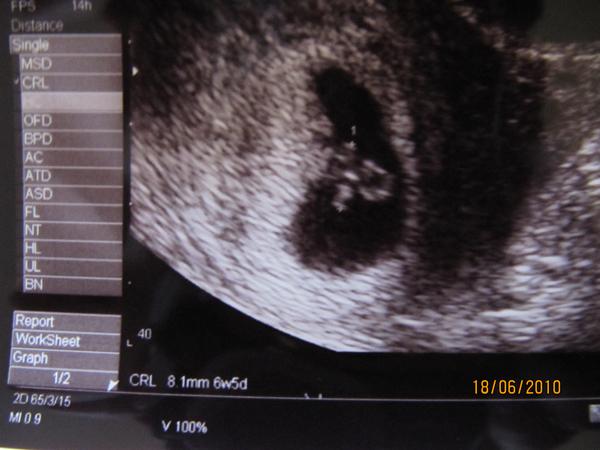

12 hetes UH: nálunk az az utolsó hüvelyi UH, tehát én még arra készülök, bár tegnap is megkérdeztem a dokim, hogyan vetkőzzek, felhúzzam, vagy lehúzzam